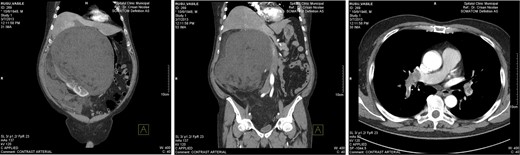

The first is the case of a 65-year-old man without significant personal history who presented to the general practitioner with a progressively distended abdomen associated with weight loss, fatigue and dyspnoea. Abdominal ultrasonography and contrast-enhanced abdominal computed tomography (CT) found a voluminous, mixed-density mass located retroperitoneally in the right perirenal area; the mass was approximately 39 × 39 × 38 cm in size, with clearly defined, irregular margins and a few visible vessels, and was subsequently identified macroscopically as a right renal angiomyolipoma. The mass was in contact with the pancreas (displacing the cephalic and corporeal sides of the pancreas), the stomach (the distal third), the aorta, the liver (the visceral side), the gallbladder, the ascending and transverse colon, the inferior vena cava and the portal vein. The mass occupied the entire right hemi-abdomen, compressing the abdominal organs, displacing the liver cranially above the sixth rib and compressing the large vessels (Fig. 1). Thoracic CT revealed the presence of pulmonary emboli (Fig. 2), for which we initiated specific therapy.

Thoracic and abdominal CT—right perirenal retroperitoneal liposarcoma with massive secondary thromboembolism.